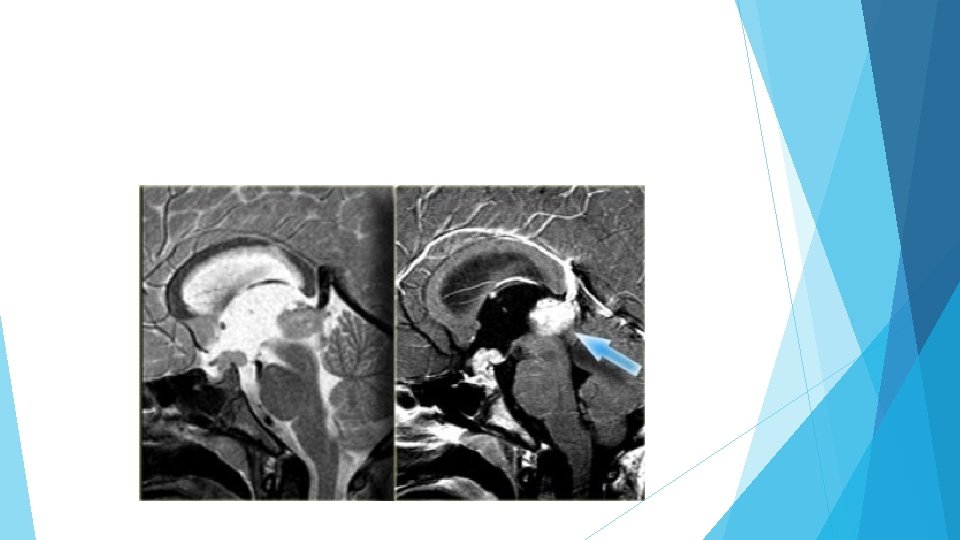

Hamartoma Hamartomas are masses of dysplastic tissue found almost exclusively in young children. One of the most common locations is the floor of the third ventricle. They are benign lesions, but patients do succumb to them because of the bad location.

Hamartoma (non-enhancing)

Sagittal T 1 with gad is the best for diagnosis of hamartoma